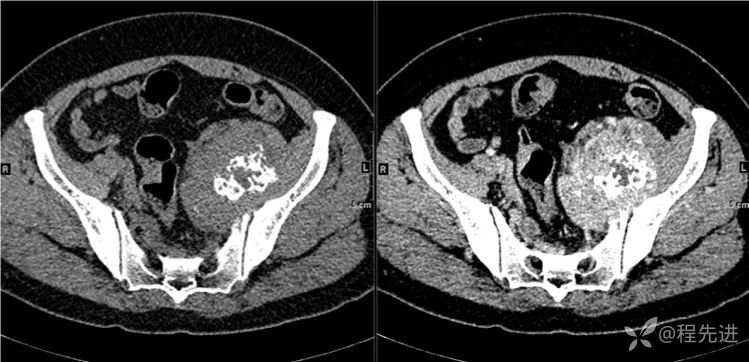

CT

- 是软组织肿瘤累及骨质还是骨肿瘤伴软组织肿块?

- 是软骨基质钙化,还是肿瘤骨?抑或钙化?

- 肿瘤的定性诊断?